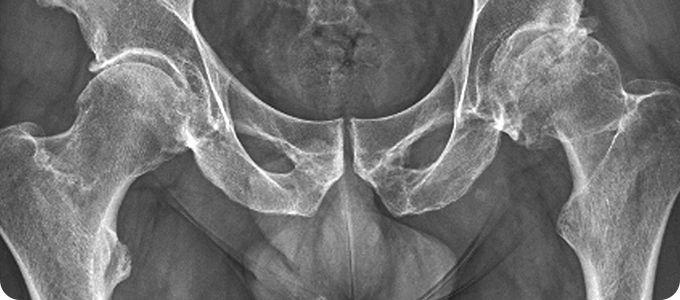

고관절골절

• 허벅지 뼈와 골반의 연결 부분인 고관절에 금이 가거나 부러지는 것입니다.

골절이 발생하면 환자의 움직임이 제한되어 대부분의 시간을 누워 있게 되므로

욕창, 폐렴, 뇌졸중, 심근 경색, 인지 능력 저하 등의 합병증이 나타날 수 있습니다.

• 대부분 넘어지면서 고관절부의 외측을 직접 부딪히면서 발생합니다.

젊은 연령에서는 추락이나 교통사고 같은 고에너지 외상에 의한 것이 대부분입니다.

노인들은 골다공증으로 인해 가벼운 낙상에 의해서도 뼈가 부러질 수 있습니다.

• 골절 후 즉시 허벅지 바깥쪽과 사타구니에 심한 통증이 있습니다.

다리를 움직일 수 없습니다. 고관절을 움직일 경우 더욱 심한 통증이 나타납니다.

골절된 쪽의 다리가 반대쪽에 비해 짧아지며, 발과 무릎이 바깥쪽으로 돌아가있습니다.